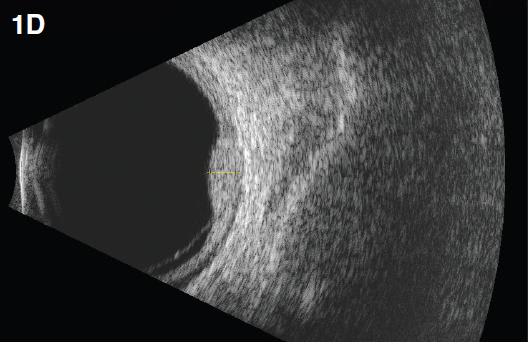

On B-scan ultrasonography, a circumscribed hemangioma appears as a dome-shaped choroidal mass with smooth contours (Figure 1d) and high internal reflectivity on Ascan (Figure 1e).

Figure 1. Circumscribed choroidal hemangioma. A 45-year-old female presented with reduced vision in the right eye (20/40). A fundus exam revealed a dome-shaped choroidal mass (A). ICG demonstrated early hyperfluorescence (B, 1:15 minutes). Note hypofluorescence (washout of dye) with a hyperfluorescent rim in the late phase (C, 12:20 minutes). A dome-shaped choroidal mass with smooth contours was observed on B-scan ultrasonography (D) with high internal reflectivity on A-scan (E). One year after treatment with PDT, fundus evaluation showed a regressed hemangioma (F), which was confirmed on B-scan ultrasonography (G). Visual acuity improved to 20/20.